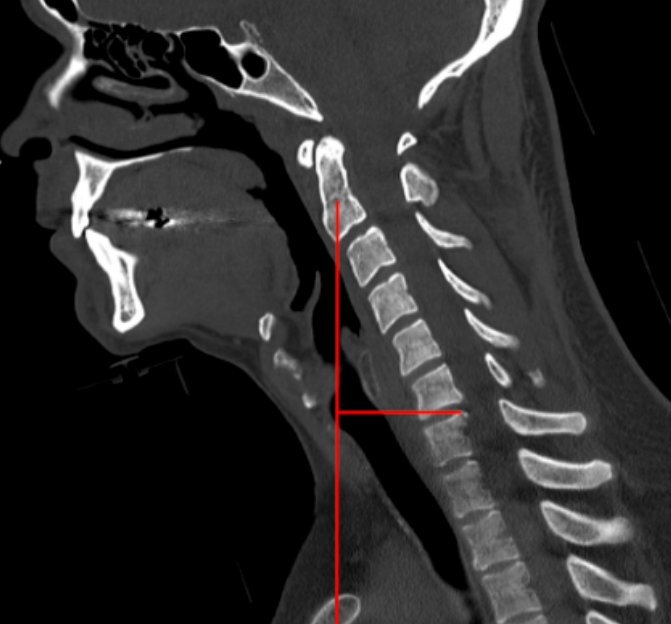

CT Scan

Sagittal Vertical Axis (SVA)

Cervical sagittal vertical axis (SVA) quantifies the anterior–posterior global alignment of the cervical spine by measuring the horizontal offset between a cranial reference point and a caudal cervical landmark. It reflects the forward or backward translation of the head over the cervical spine and is a key parameter in the evaluation of cervical sagittal balance, deformity, and postoperative outcomes.

• Obtain a true mid-sagittal CT reconstruction showing the skull base through C7.

• Identify the center of the C2 vertebral body.

• From this point, drop a vertical plumb line parallel to the vertical axis of the image.

• Identify the posterior–superior corner of the C7 vertebral body.

• Measure the horizontal distance (mm) between the C2 plumb line and the posterior–superior corner of C7.

• Record this value as the C2–C7 SVA.

• Normal sagittal alignment: ≤ 20 mm

• Mild anterior malalignment: 21 - 40 mm

• Severe sagittal imbalance: > 40 mm